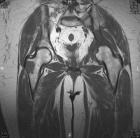

63 year old female complains of increasing left hip pain after a fall three weeks ago

History of breast cancer